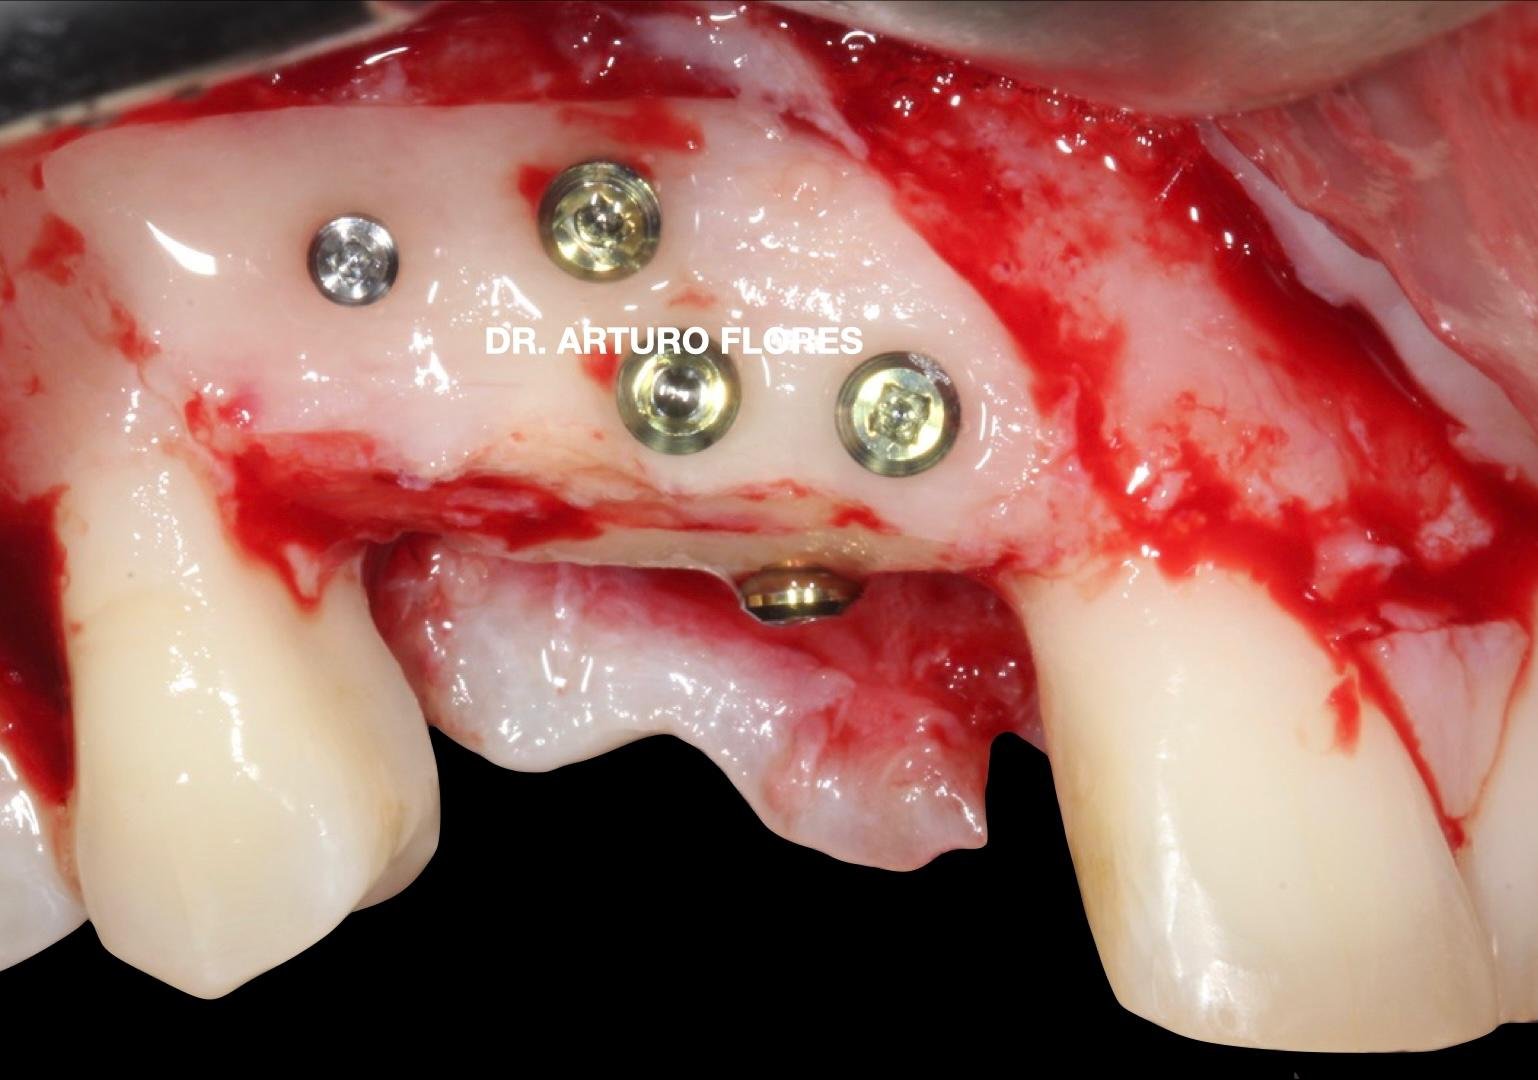

Me considero un auténtico enamorado de la cirugía implantológica. Cuanto mayor es el reto quirúrgico, mayor es mi motivación para enfrentarme a él y resolverlo. La planificación quirúrgica y la documentación de los casos son las claves para conseguir el resultado que se merecen mis pacientes

En una estancia clínica conmigo es habitual ver casos relacionados con regeneraciones óseas complejas con el manejo de todas las técnicas, incluida la del profesor Khoury. También podrás aprender a manejar los tejidos blandos para reconstrucción de tejidos y cobertura de recesiones.

¿Qué tratamientos se pueden presenciar? Regeneraciones óseas complejas con el manejo de todas las técnicas, incluida la del profesor Khoury. También podrás aprender a manejar los tejidos blandos para reconstrucción de tejidos y cobertura de recesiones.